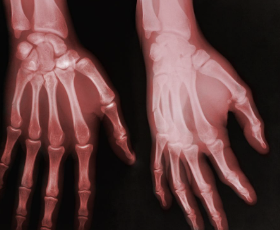

손가락 관절염 초기증상 원인 치료방법 등 정보에 대해 정리해드리도록 하겠습니다. 손가락 관절염은 손가락 마디에 통증이나 염증이 생기는 질환입니다. 손가락 관절염의 원인은 나이가 들면서 관절의 연골이 닳거나, 부상이나 염증으로 인해 관절이 손상되는 경우가 있습니다. 손가락 관절염은 삶의 질을 떨어뜨리고, 일상생활에 불편을 주는 문제입니다.

손가락 관절염의 초기증상으로 나타날 수 있는 것은 손가락 변형입니다. 손가락 변형은 염증과 굳은살로 인해 관절이 비정상적인 방향으로 꺾이거나 비틀리는 것입니다. 손가락 변형은 주로 중지와 약지에 자주 발생하며, 보통 반대쪽으로 구부러지거나 안쪽으로 꺾이는 형태를 띱니다. 손가락 변형은 통증과 부기 외에도 손가락의 기능을 저하시키거나 미관을 해치는 등의 문제를 일으킬 수 있습니다.